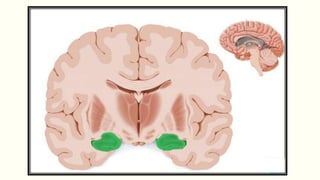

Papez Circuit

Control of emotional expression

Memory storage

Hippocampus

Mammillary

bodies

Mammillothalamic

tract

Anterior

Thalamic Nuclei

Cingulate Gyrus

Parahippocampal

gyrus